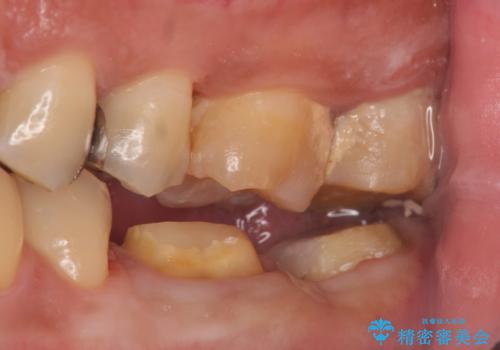

- 左下7の歯しみる、被せ物を被せてもすぐに外れてしまうといらっしゃった方の症例です。

左下に被せ物を被せるクリアランス(補綴のための上下のスペース)ないため、十分な歯冠長を確保するため歯冠長延長術を行いました。

その後歯肉の回復を待ち、フルジルコニアクラウンにて補綴を行いました。